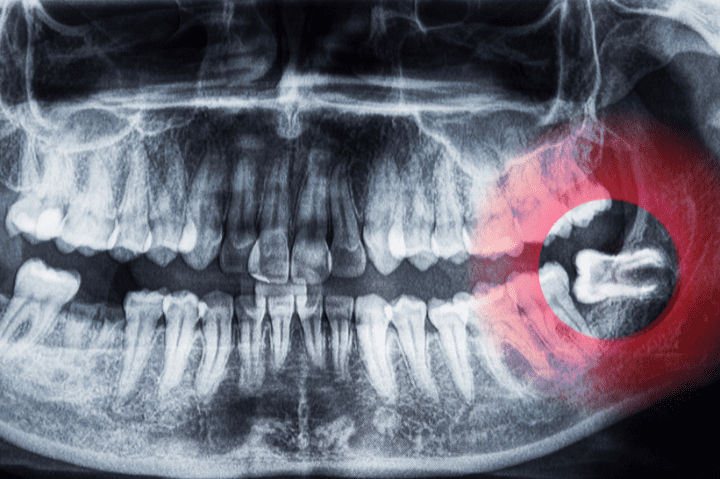

Wisdom teeth (third molars) typically emerge between ages 17 and 25. Because most mouths don’t have enough room to fit them properly, wisdom teeth often lead to:

• Impaction (trapped under the gums)

• Pressure on nearby teeth

• Swelling or infection

• Jaw or gum discomfort

Not everyone needs their wisdom teeth removed, but if they begin causing problems—or are likely to—we may recommend extraction to prevent future issues. At Tooth Harmony, we use detailed imaging to evaluate your wisdom teeth and provide guidance based on your individual needs.

1. Assessment & explanation – We’ll review X-rays, discuss your symptoms, and outline your options.